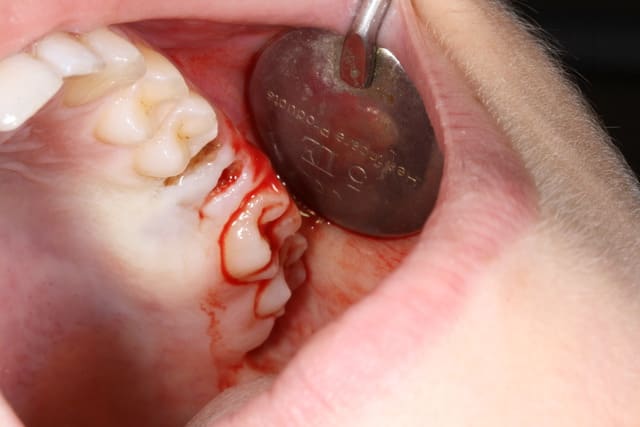

J'ai accueilli cette patiente un peu phobique , fait une anesthésie , une avulsion , un curetage de l'alvéole qui contenait de la pâte canalaire , le tout avec application de façon à ne pas pénétrer le sinus , vérifier une possible CBS , et suturer le tout .